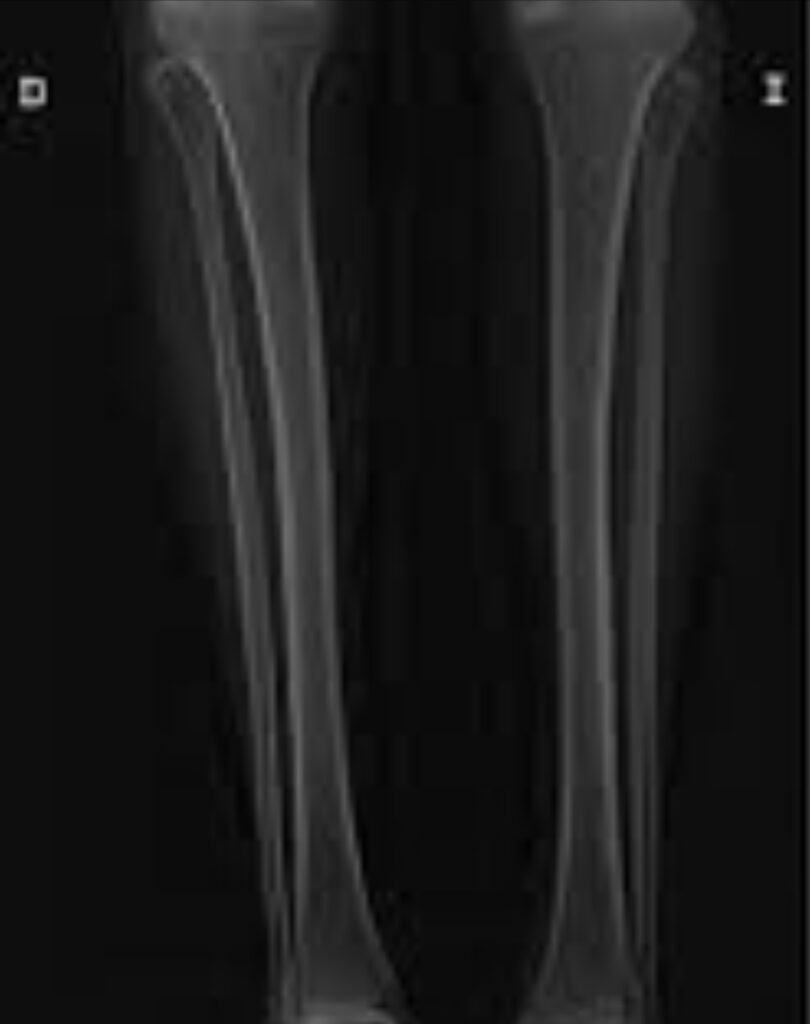

La osteomalacia puede presentarse con dolor óseo y articular, junto con disminución de la fuerza y resistencia musculares. Pueden ocurrir fracturas patológicas con traumatismos pequeños o sin traumatismos.

La densitometría ósea ayuda a documentar el grado de osteopenia.